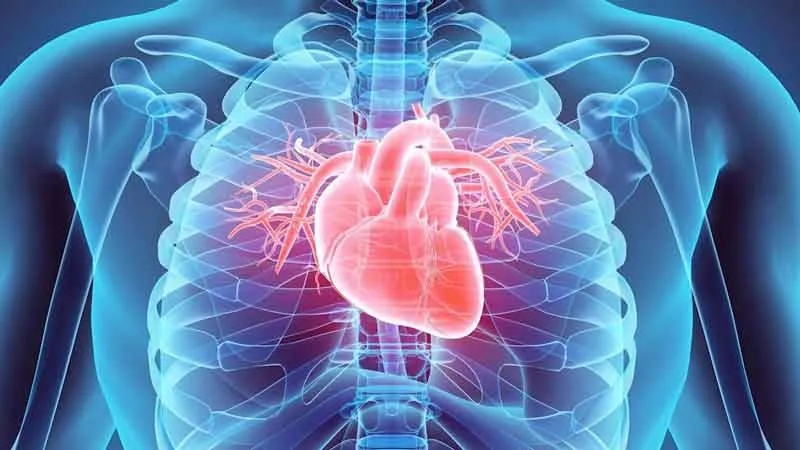

La cardiología es la rama de la medicina encargada del diagnóstico, tratamiento y prevención de las enfermedades del corazón y del sistema circulatorio (vasos sanguíneos). Los cardiólogos tratan condiciones como infartos, insuficiencia cardíaca, arritmias e hipertensión, utilizando pruebas como electrocardiogramas y ecocardiogramas para mejorar la salud cardiovascular.

estudiar, diagnosticar y tratar las enfermedades del corazón y del sistema circulatorio (vasos sanguíneos). Se enfoca en la prevención, diagnóstico (electrocardiograma, ecocardiograma) y tratamiento de condiciones como infartos, arritmias, insuficiencia cardíaca e hipertensión arterial.